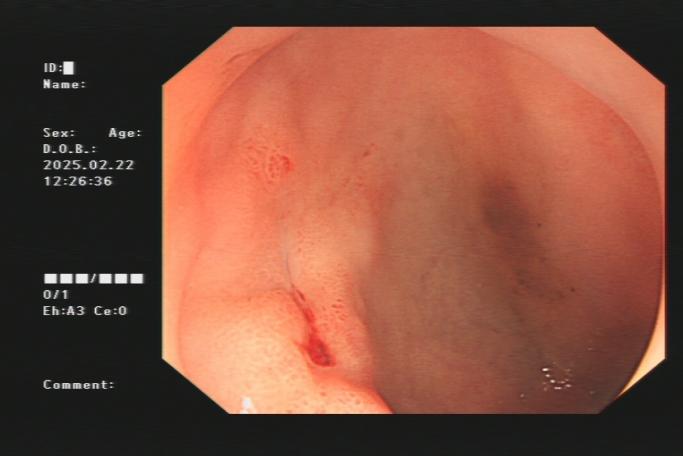

2.小肠出血:小肠出血可以由消化道自身疾病所致,也可由全身疾病及使用治疗药物后引发。年龄是重要因素,不同年龄小肠出血的病因不尽相同。年轻病人(16~40 岁)常见病因有克罗恩病、小肠腺瘤、梅克尔憩室、Dieulafoy 病;中年病人(41~65 岁)常见病因有血管病变、 小肠肿瘤、非特异性肠炎、肠道溃疡、药物相关性出血等;老年病人(>65 岁)常见病因有血管病变、 NSAIDs 相关性溃疡、小肠肿瘤等。以下是小肠出血内镜图片:

回肠末端出血及肠镜下止血夹止血